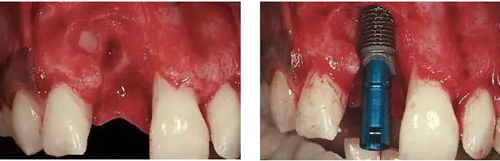

圖3、拔牙后看到更大范圍的骨缺損,并且缺損導(dǎo)致上頜側(cè)切牙根尖牙骨質(zhì)暴露,繼而存在術(shù)后由于軟硬組織退縮而帶來的美學(xué)風(fēng)險(xiǎn)。

圖4、植入的種植體,初始穩(wěn)定性很好,由于骨缺損范圍大,選擇潛入式愈合。

圖5、種植體完全位于拔牙窩骨壁包圍的范圍內(nèi),距離唇側(cè)骨板至少2mm。